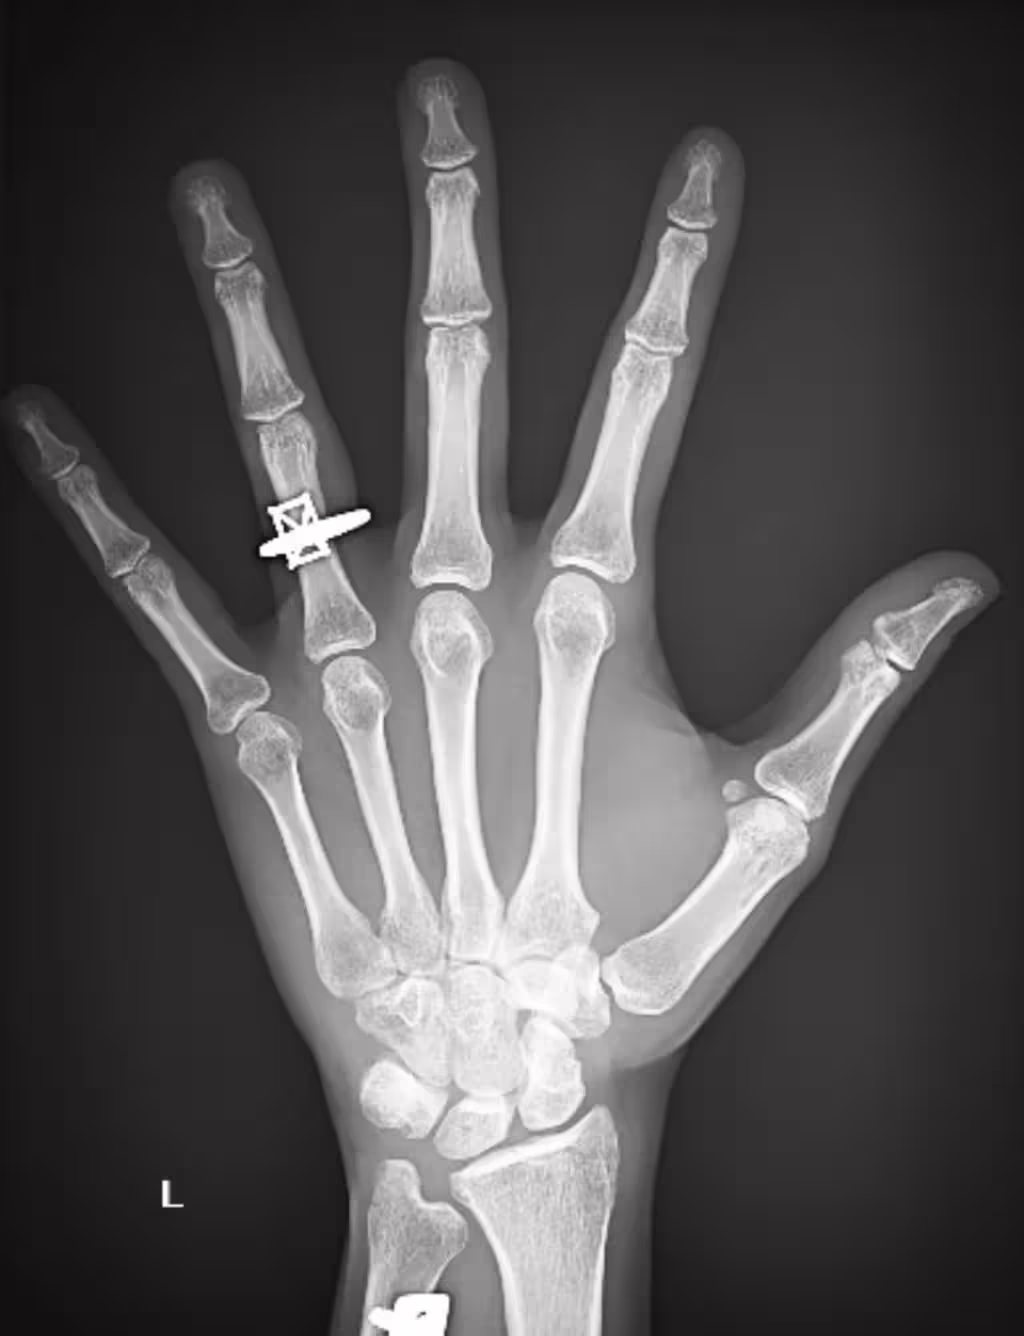

根據《時人》報導,當天賈斯汀幫忙預約看診並陪著女友進診間,安娜伊絲覺得男友很體貼,完全沒有起疑。3位醫護人員進診間時,安娜伊絲還想說只是個小傷,怎麼需要那麼多人來。當醫師在螢幕上秀出一張左手X光片,安娜伊絲才驚喜發現,X光上的無名指竟然多一枚戒指。這對情侶交往2年,賈斯汀幾個月前就想求婚了,早就準備好一枚3.47克拉的鑽戒,但遲遲等不到開口的好時機。

直到這天女友摔傷手,賈斯汀靈機一動決定在CityMD診所求婚,迅速向醫護人員說明求婚計畫,提前取得醫療團隊的幫助。安娜伊絲看到X光後,賈斯汀拿出戒指單膝下跪求婚成功。安娜伊絲感動落淚:「感覺好不真實!賈斯汀的求婚太神奇了,我這輩子從沒那麼驚喜過!」